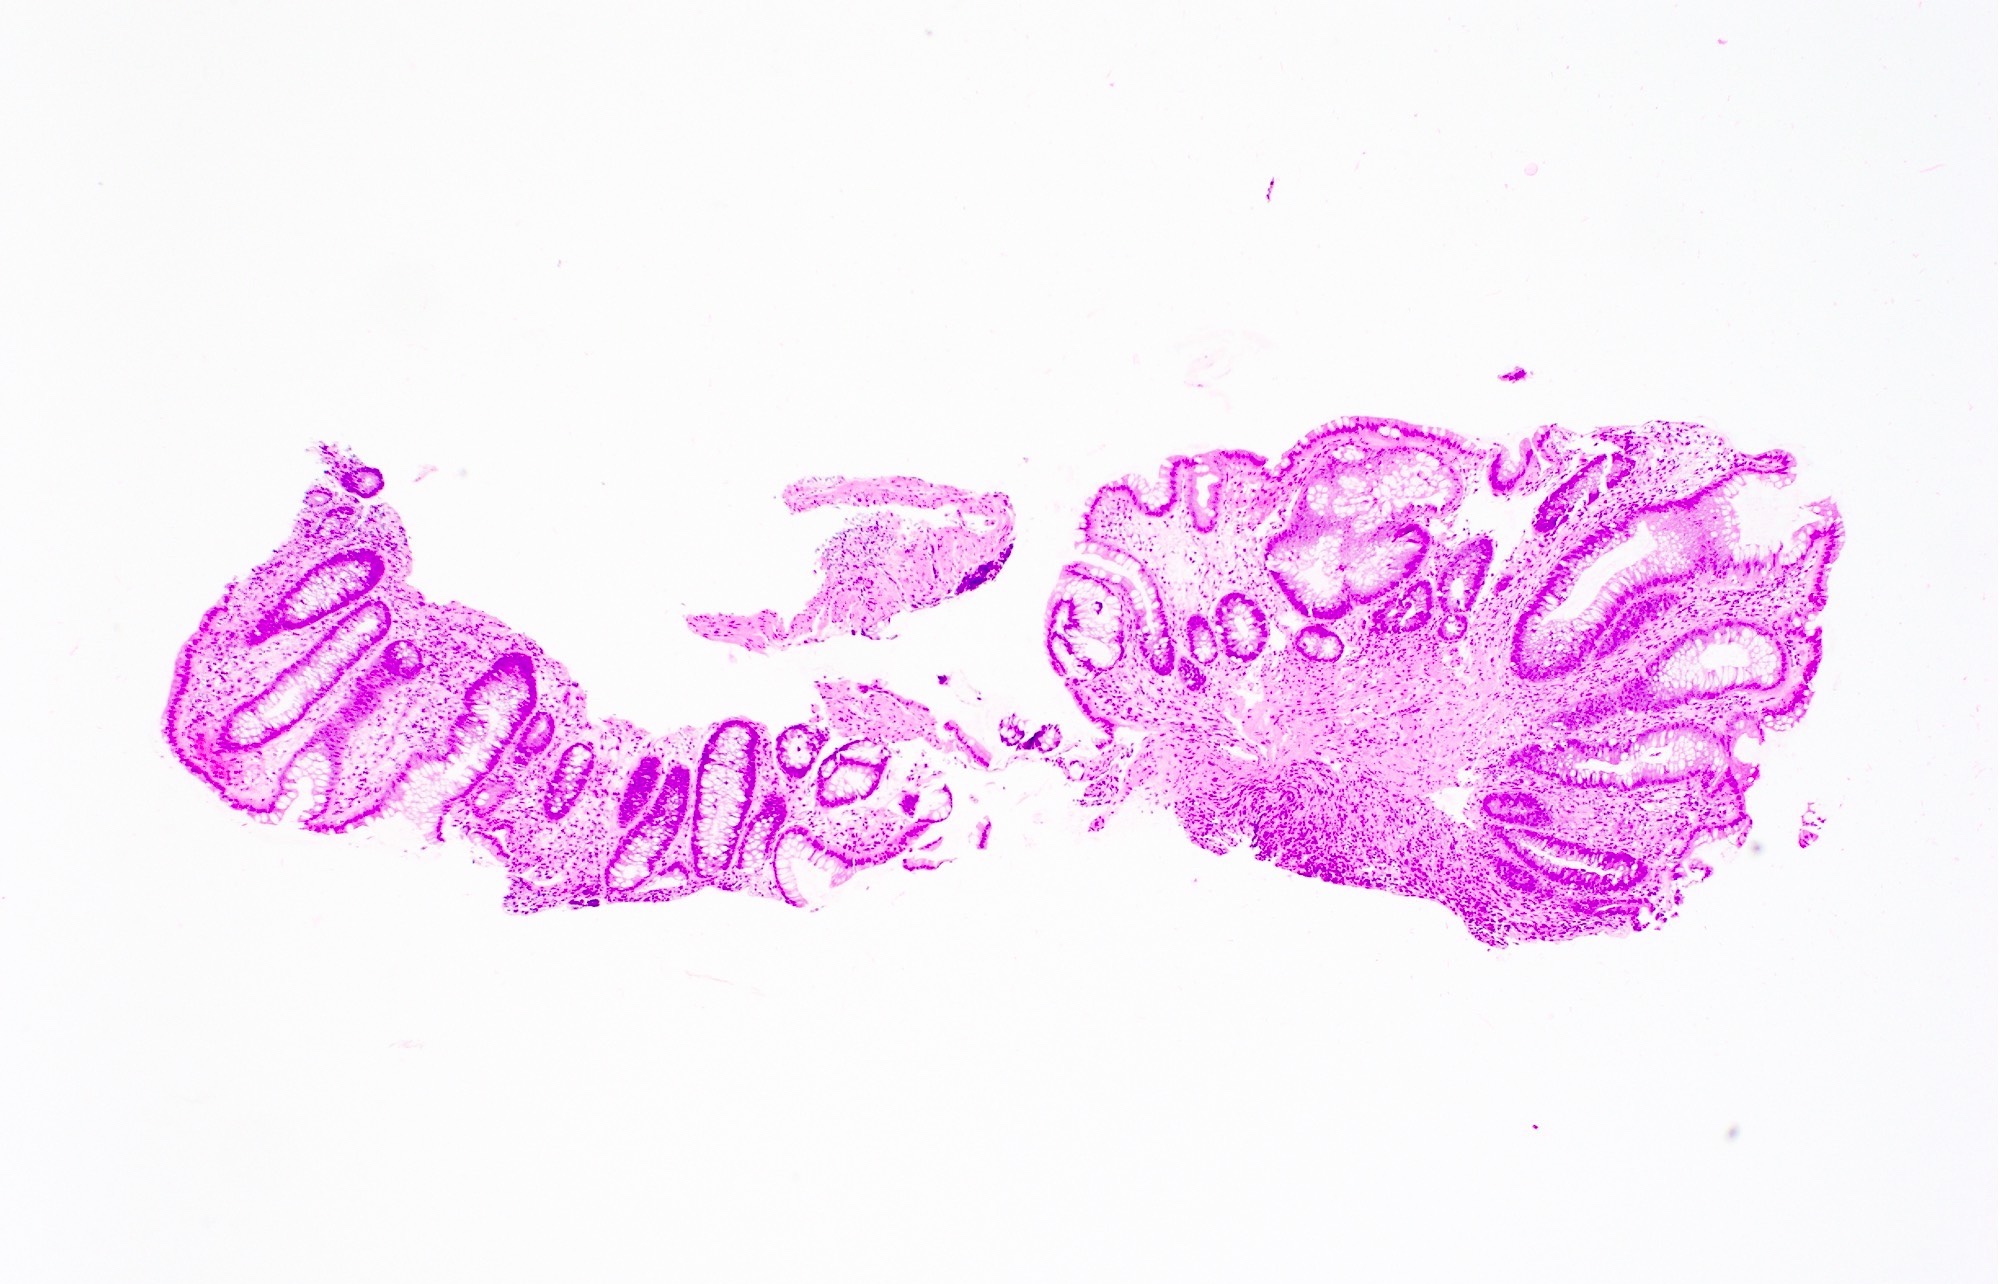

Microscopic (histologic) images

Virtual slides